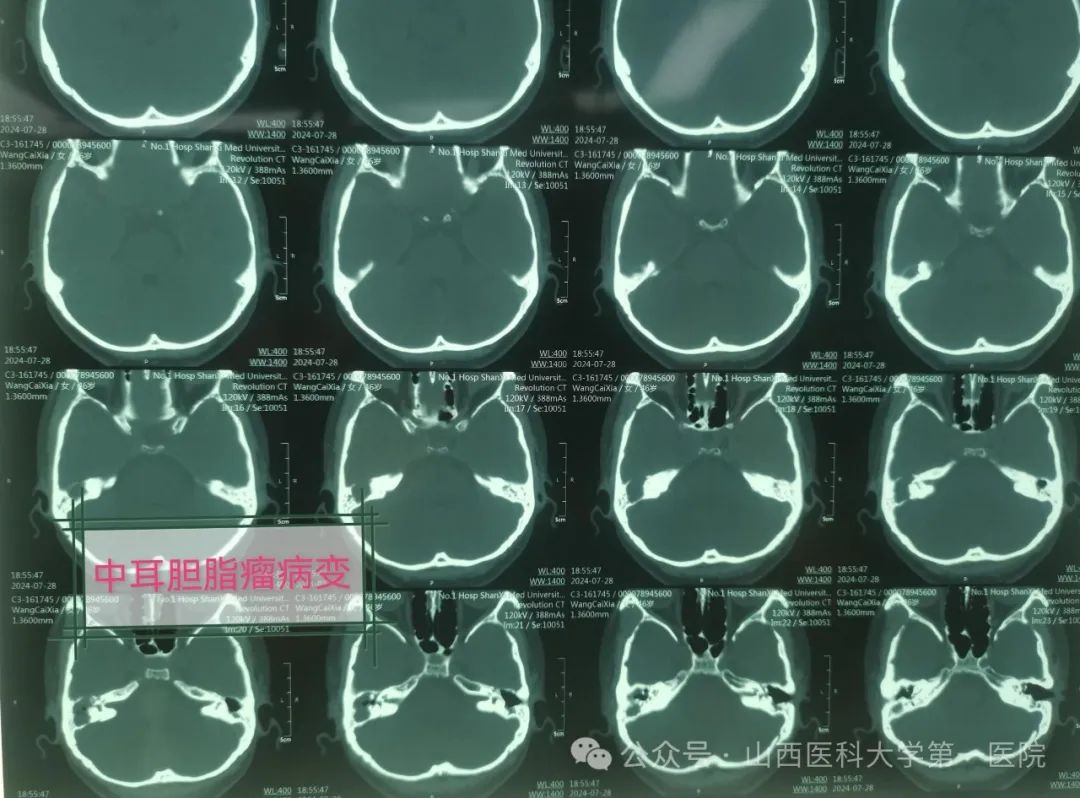

耳鼻咽喉-头颈外科,做影像学相关检查后被医生确诊为中耳胆脂瘤、面神经麻痹、迷路炎与迷路瘘管、局限性脑膜炎。

主刀医生张海利教授介绍,慢性化脓性中耳炎属于耳科常见疾病,而中耳炎胆脂瘤属于其中较为危险的一种类型。胆脂瘤并非平时所说肿瘤,是位于中耳与乳突腔内囊性结构,有脱落上皮细胞堆集、中央坏死,像滚雪球一样,越聚越大而形成。胆脂瘤患者临床上可出现耳流脓、耳痛、耳闷塞感及听力下降等症状,耳流脓一般呈持续性或间断性,有特殊恶臭味,有时伴有血性分泌物。胆脂瘤具有潜在危害,逐渐增大时会压迫并侵蚀周围骨质,并向邻近组织扩散,严重者可出现脑膜炎、眩晕以及面瘫等颅内外并发症。此例中年女性患者胆脂瘤破坏范围较大,中颅窝脑板已经破坏,形成局限性脑膜炎并发症,而且现在已有偏头痛的症状,同时在手术中发现内耳水平半规管与后半规管破坏,形成迷路瘘管与迷路炎,面神经骨管裸露破坏,医生在显微镜下仔细清理病变组织包括胆脂瘤与肉芽组织,经过乳突根治、面神经减压以及内耳迷路修补治疗,手术获得圆满成功。术后,张女士病情得到基本控制,经过消炎消肿抗感染以及对症治疗后即可出院。